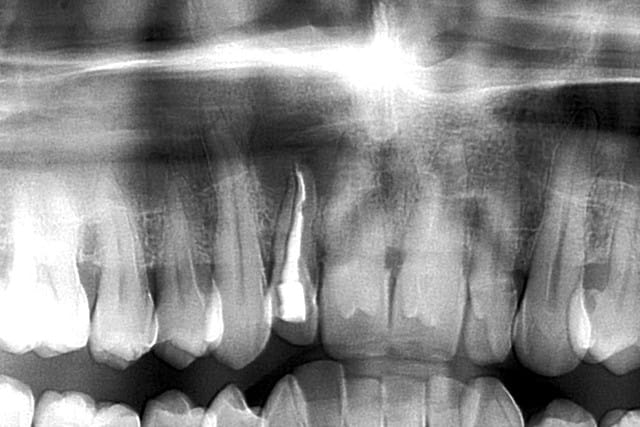

en 1997...ce patient vient pour un contrôle...quelques soins à faire...et découverte à la pano d'une lésion sur 12...

endo...et rdv 6 mois plus tard pour contrôler l'évolution...jamais honoré...

ce patient revient...13 ans plus tard..."docteur, y a ma dent qui bouge...faites quelque chose..."

pano....youpie...scan...et là je crois qu'on décroche le ponpon...

super sinus...bien sûr la dent est condamnée...mais vous feriez quoi pour avoir une chance de planter dans quelques mois...ou du moins éviter un "énorme" défaut osseux qui sera difficilement gérable d'un point de vue esthétique...???

PS...désolé pour la qualité de la première pano...pas du numérique à l'époque...

t'as vu la taille du kyste??? il va jusqu'au sinus et se prolonge derrière la 11...la 12 ne tiens que par son ligament palatin...

un ptit zoom sur la pano...en renforçant le contraste...